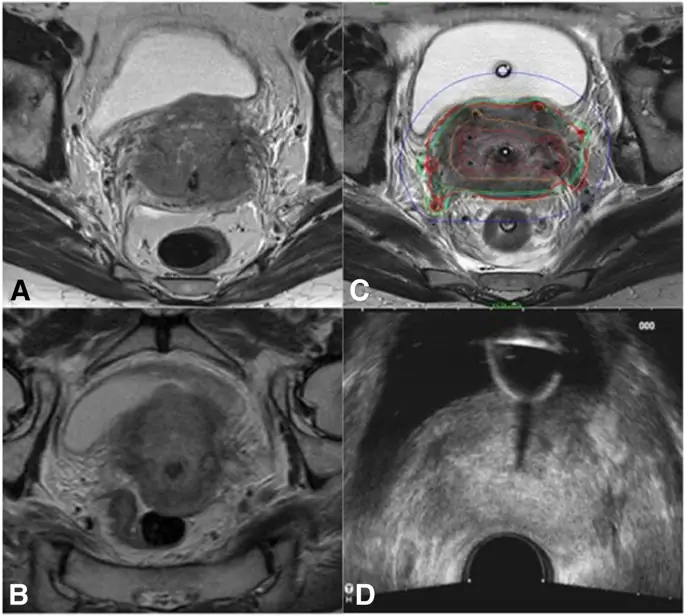

Еще одна причина может зависеть от формы и типа опухолевого роста. Очень прогрессирующие стадии опухоли (FIGO IVA) показывают более вероятный инфильтративный рост с неправильными формами и тонкими оцифровками, которые глубоко проникают в параметрическое пространство по сравнению с объемными экспансивными опухолями шейки матки, которые обычно более отчетливо видны при визуализации TRUS (фиг. 2 и 3).

Случай рака шейки матки FIGO стадии IVA, потому что инфильтрация мочевого пузыря с плохим ответом на EBRT с хорошим согласием между preBT MR и preBT TRUS в измерениях опухоли. Опухоль во время диагностического МР (а), во время МРТ до бТ (б), во время первой брахитерапии (в) и во время ТРУЗИ до БТ (г)

Изображение в полном размере